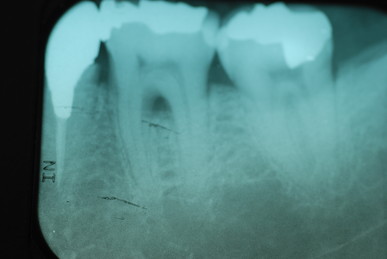

左下の一番奥の歯の治療がいい加減なようです。

左下の一番奥の歯の治療がいい加減なようです。しかし治療をしてみると滅菌しながら治療をすることの困難さを痛感しました。

三本ある根管の内、難しい手前の根幹の治療が為されていません。顎の骨に黒い影ができています。

骨の部分は健康を回復しています。影がありません。治療が成功しています。

上のレントゲンでも歯根の間に影があります。悪性の分岐部病変ですね。